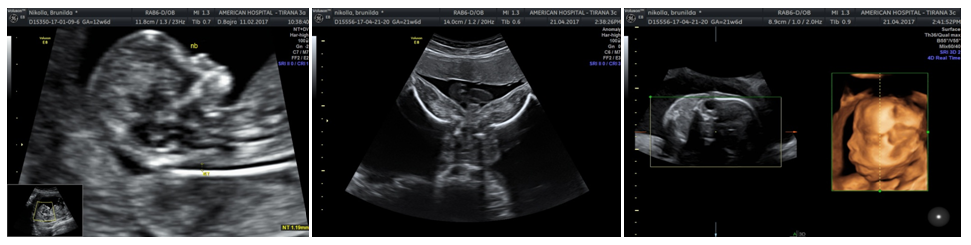

Interpretation: Male fetal profile with duplication in chromosome 6 in region 6q23.2 and duplication in chromosome 21 in the region 21q22.12 (Figure1).

Figure 1 Complex of abnormal ultrasound findings.

Our case showed morphological features more similar to the mutations of the chromosome 21 than the mutations of chromosome 6. This might be due to the length and the site of the duplicated chromosome (Figure2).

Figure 2 Prenatal diagnosis of an abnormal fetus.